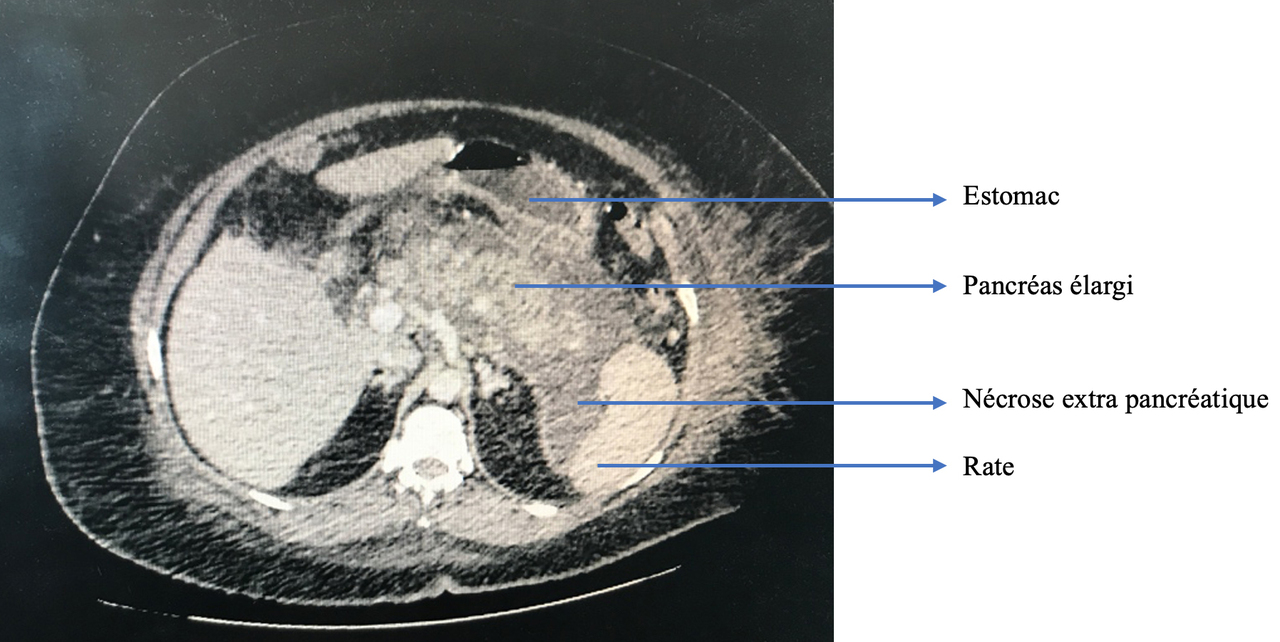

La douleur de la pancréatite est épigastrique irradiant dans le dos, majorée par la respiration profonde et la position antalgique est en chien de fusil.